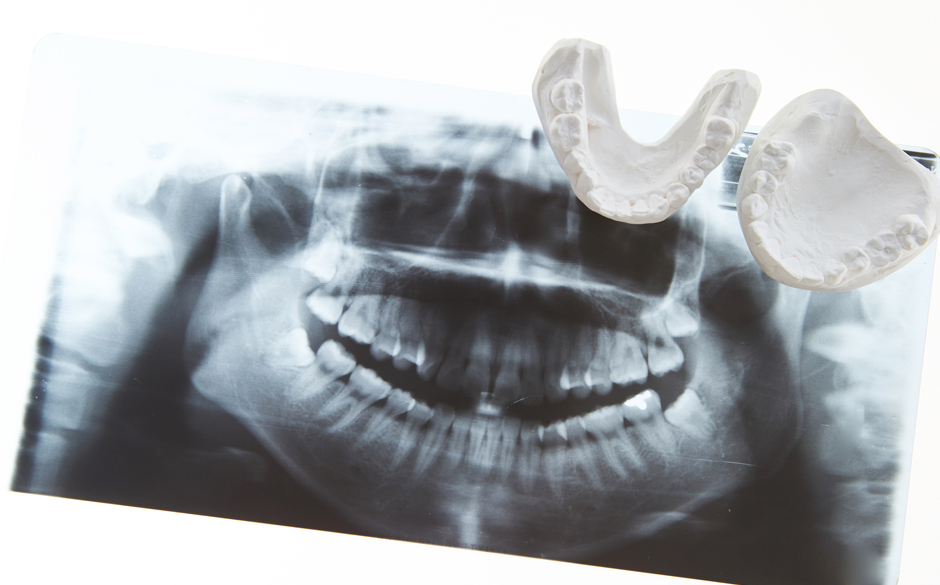

より快適な入れ歯を作るには

まずは精密検査

お持ちの入れ歯に違和感がある場合は、かみ合わせや顎の構造をあらためて測定し、データ化します。その問診結果を確認しながら、問題点を洗い出します。

治療用の入れ歯を使うことも

より精密な入れ歯を作るには、まず治療用の入れ歯を用意して、かみ合わせの高さや顎の位置、歯ぐきの状態など、お口全体のかみ合わせを整える必要があります。そうしてかみ合わせの調整ができてから最終的な入れ歯を製作することで、よりフィット感にすぐれた入れ歯を作ることができます。

入れ歯製作の流れ

精密検査・カウンセリング

まずは、かみ合わせや顎の状態を詳細に検査し、お悩みやご希望をしっかりとうかがいます。その結果をもとに、お一人お一人に合った入れ歯の種類や素材、治療法、費用の目安について丁寧にご説明。内容にご納得いただけたら治療を進めてまいります。